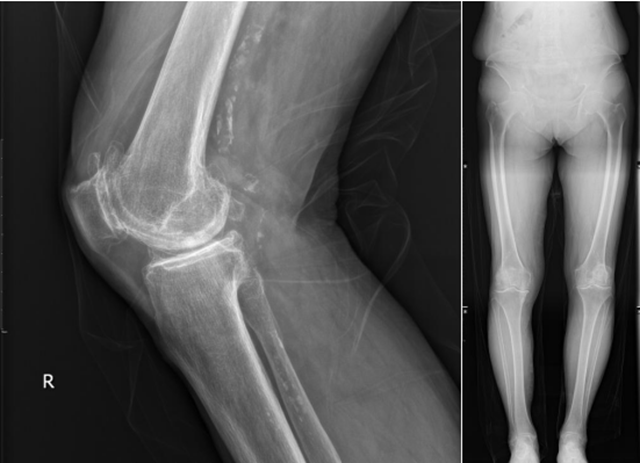

术前X线提示右膝关节内侧间隙软骨严重磨损、关节间隙严重狭窄、膝关节内翻畸形

1月前,李婆婆膝关节疼痛加重,家属带她来到西南医科大学附属中医医院就诊,大骨科主任兼骨伤科关节·足踝组扶世杰教授接诊后为其完善了CT、核磁共振等相关检查,发现其右膝关节软骨严重磨损,关节间隙严重变窄,膝关节屈伸活动严重受限。